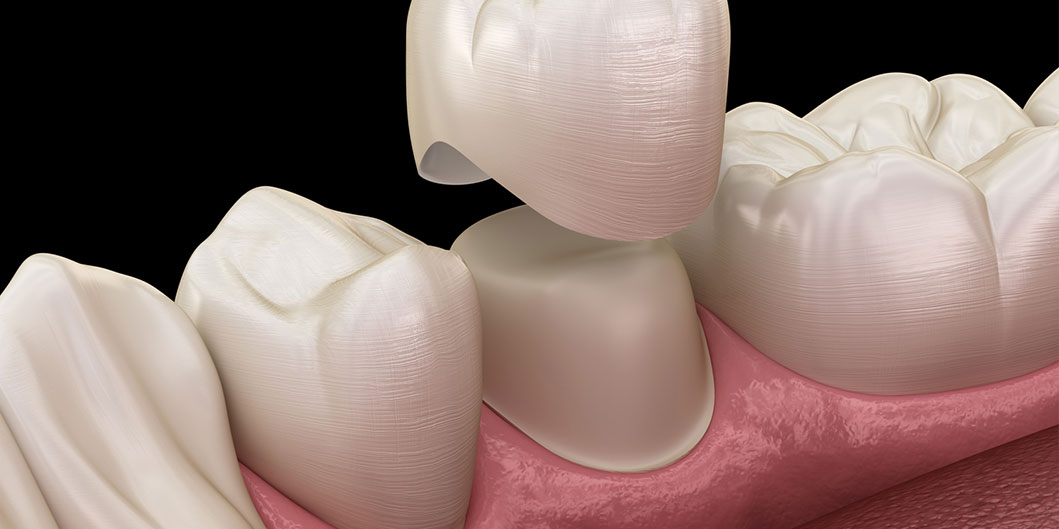

Zirkonyum kuron, olağanüstü gücü ve estetik nitelikleriyle bilinen bir malzeme olan zirkonyum oksitten yapılan bir diş kuronu türüdür. Bu kuronlar hasarlı, çürümüş veya zayıflamış dişleri kaplamak, şekillerini, boyutlarını ve işlevlerini geri kazandırmak için kullanılır. Ayrıca diş implantı restorasyonunun bir parçası olarak veya rengi solmuş veya şekilsiz dişlerin görünümünü iyileştirmek için de kullanılabilirler.

- Diş Restorasyonu: Çürük, kırık veya büyük dolgular nedeniyle zayıflamış bir dişi korumak ve güçlendirmek için.

- Diş Hazırlığı: Hasarlı diş, kuron için yer oluşturmak üzere dikkatlice yeniden şekillendirilir. Herhangi bir çürük veya eski dolgu çıkarılır ve diş kuronun yerleştirilmesi için hazırlanır.

- Kuron Yerleştirme: Kuron hazır olduğunda, hazırlanan dişin üzerine yapıştırılarak işlevi ve görünümü geri kazandırılır.